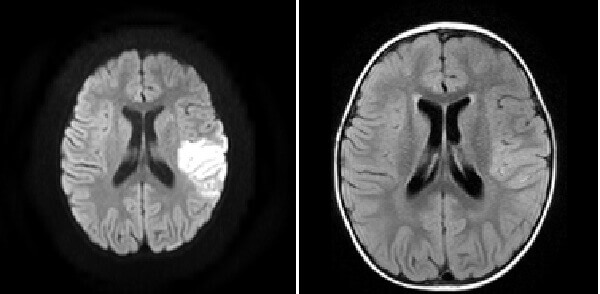

Diagnosis: MCA territory infarct

Figure 1: (a, blue arrow) increased DWI signal in the right frontal lobe is also low on ADC

b,red arrow) FLAIR images demonstrate increased cortical signal and sulcal effacement

(c, green arrow) consistent with an acute infarct.